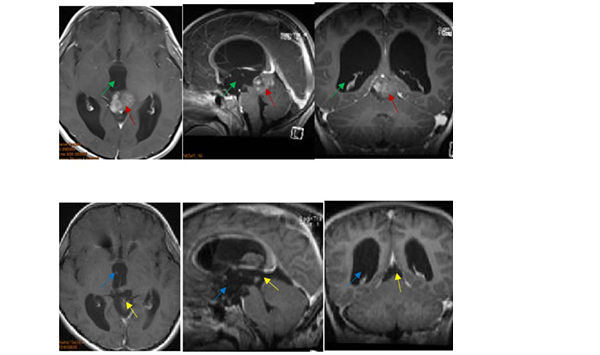

8岁小患者经德国巴特朗菲教授术前术后影像对比

对于松果体区患者来说,手术治疗的入路一般包括幕下小脑上入路、枕下小脑幕入路、后纵裂经胼胝体入路等,而更佳的手术治疗方式主要依赖于肿瘤解剖学特点的不同。针对8岁小患者这个病例,巴特朗菲教授采取的是幕下小脑上入路结合幕上枕下乙状窦旁经小脑幕入路,较终肿瘤得以全切除,且尽力减少了组织的损伤,这对预防后期肿瘤的复发起到了较大作用。